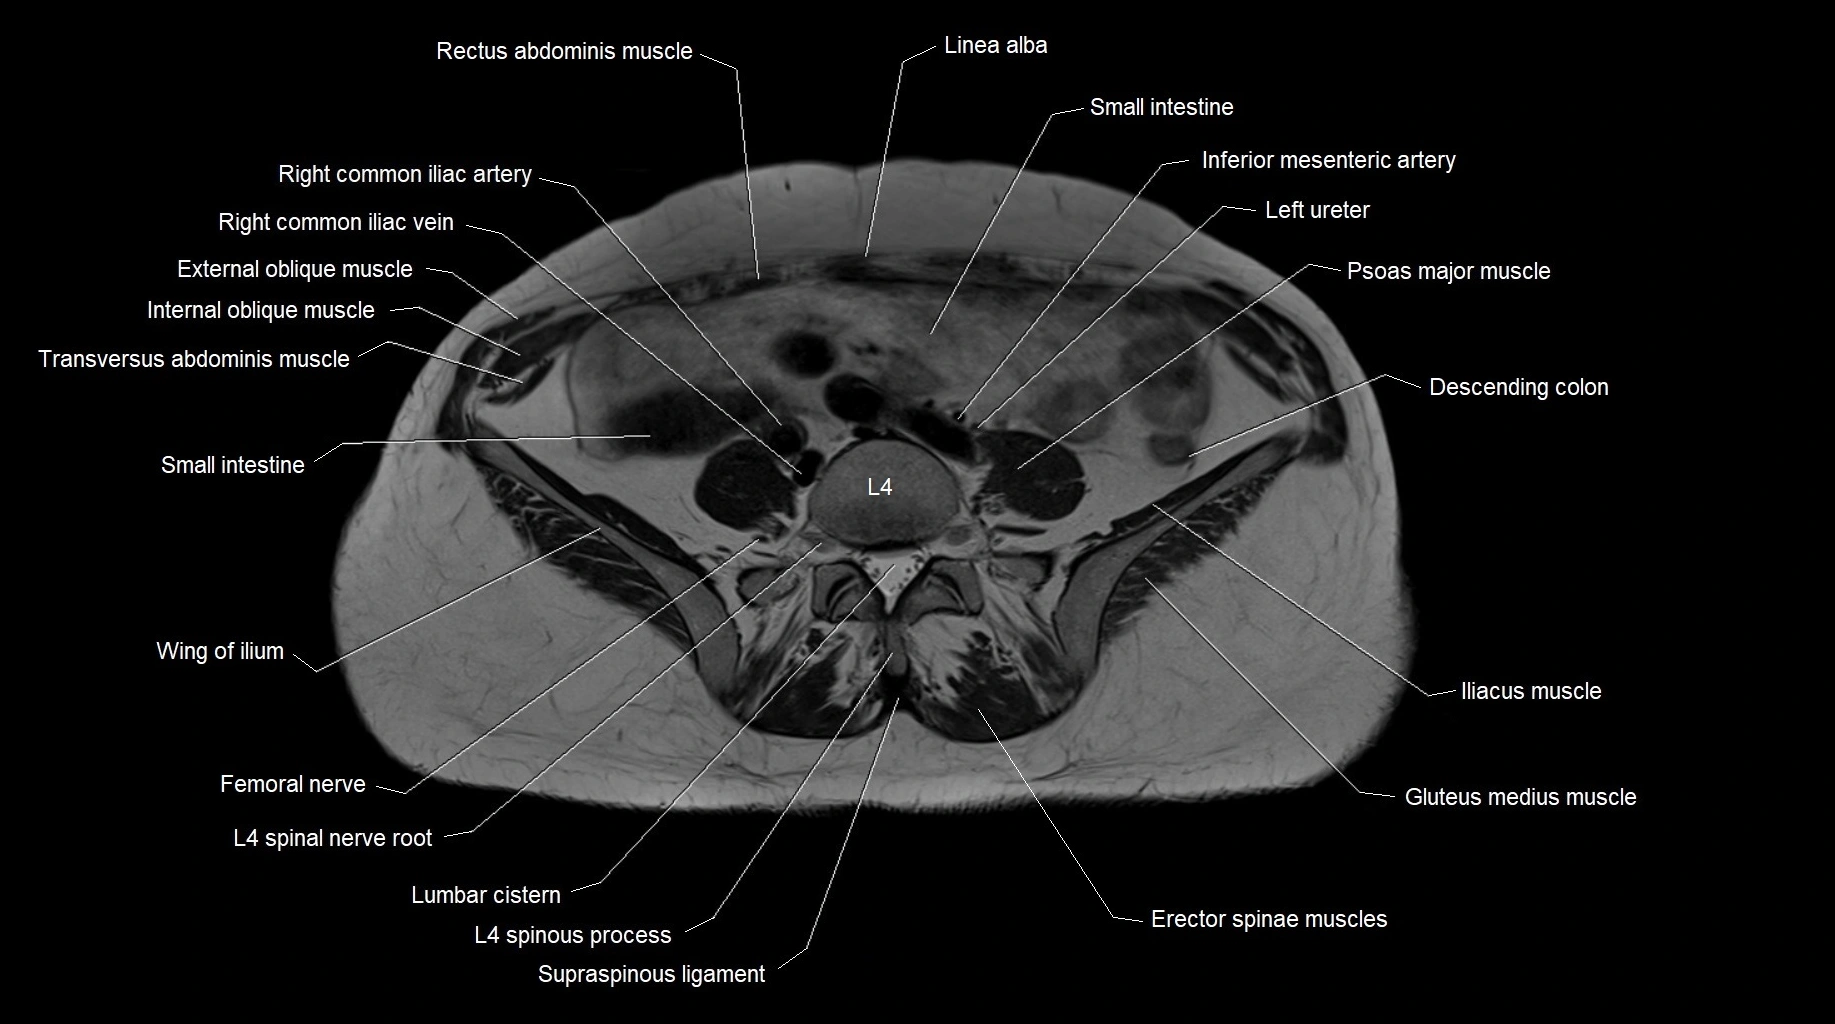

MRI images